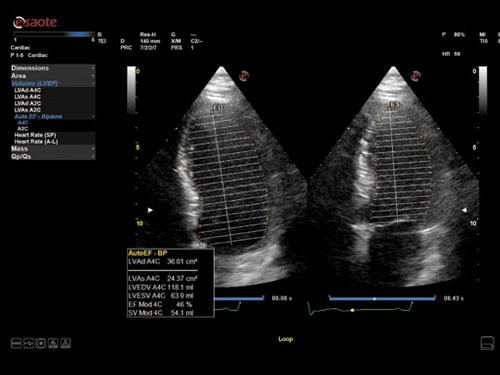

AutoEF: Automatické měření ejekční frakce (plně automatické).

Díky své výkonné platformě Windows ™ 10 se Esaote MyLab ™ X7 zaměřuje na zkrácení doby vyšetření a lepší pracovní postupy pomocí široké škály automatických procesních funkcí „nulového kliknutí“ pro zobrazování, dopplerovské zpracování, následné zpracování, měření, archivaci a připojení. Díky zpracování „nulovým kliknutím“ lze nyní rychle a snadno provádět srdeční ejekční frakci nebo fetální nuchální translucenci.